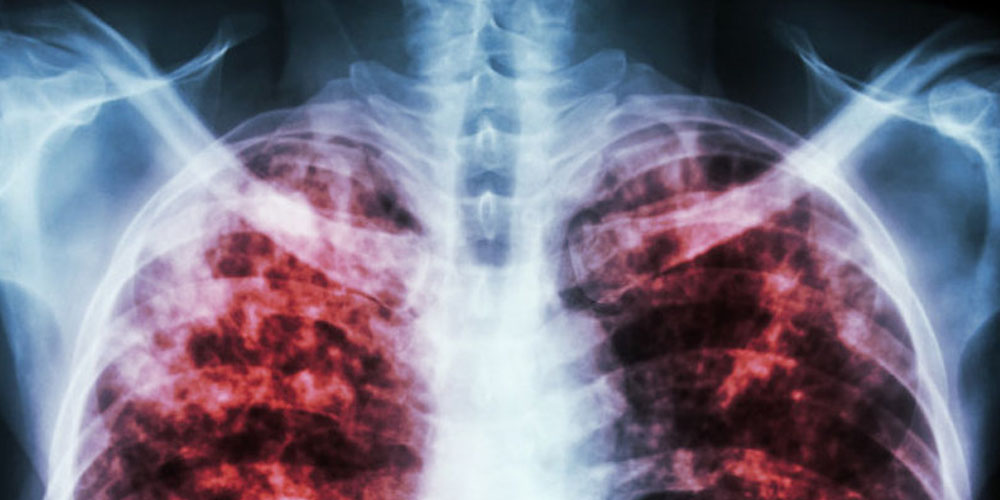

Цель мероприятия – совершенствование организации выявления туберкулеза лиц из групп риска развития по заболеванию туберкулезом в амбулаторных условиях.

Слушателей познакомили с основными эпидемиологическими показателями по туберкулезу – как среди постоянного населения города Москвы, так и среди мигрантов и социально дезадаптированных лиц; с лабораторными методами диагностики туберкулеза, в т. ч. с применением иммунологических IGRA-тестов; с современными методами скрининга на туберкулез с учетом дифференцированного подхода и индивидуальных особенностей лиц из групп риска развития туберкулеза. Уделено внимание совместной работе врачей медицинских организаций государственной системы здравоохранения города Москвы, оказывающих первичную медико-санитарную помощь взрослому населению, и врачей-фтизиатров в выявлении туберкулеза у лиц из групп риска.